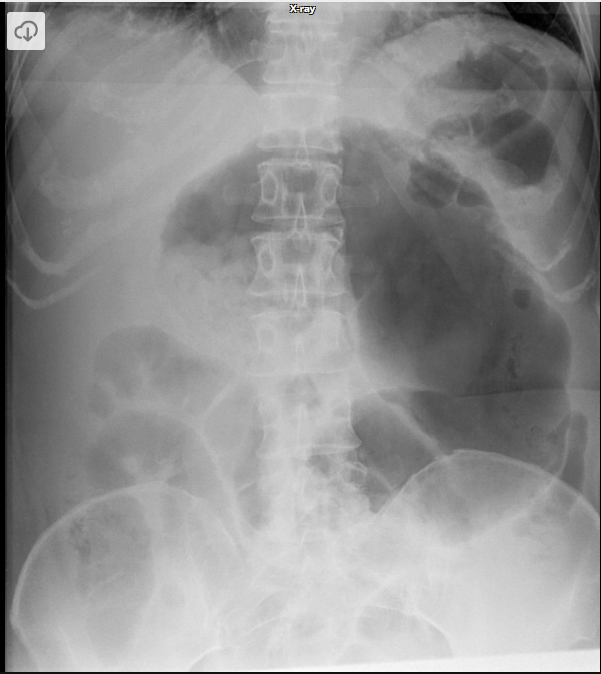

Q

Qual o nome do sinal? O que ele significa?

A

Sinal do grão de café

Volvo de sigmoide